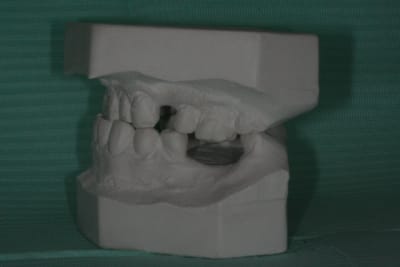

ploc, as-tu une photo de profil et bien perpendiculaire à l'arcade de ton modèle d'étude?

Il me semble, qu'éventuellement tu corriges au mieux le déport de l'obturation de la 44 en réalisant un inlay, puis je serais vraiment surpris qu'un implant ne passe pas.

j'utilise des easyimplants dont le porte implant est constitué par une tige de diametre inférieur au plus petit diametre de leur implants, çà doit passer. Si un foret de 3 mm passe et que tu as 6.4 mm d'espace entre les bases des deux dents c'est ok pour un 3.4 de diametre.

photos avant ttt et maintenant

au vue de tes photos...je reste persuadé qu'un implant de petit diamètre (entre 3 et 4 mm) devrait passer...une prémolaire fait environ 8mm...t'as un peu moins que le volume normal...disons à vue de nez 6 mm....çà passe...si tu veux peaufiner l'esthétique...au pire un petit stripping distal de 44 et mésial de 46...